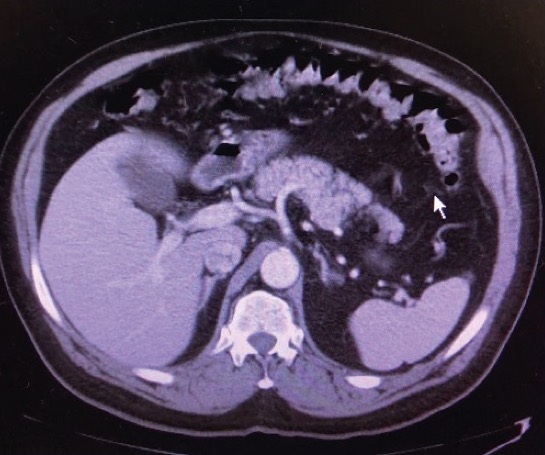

Gadolinium-Induced Acute Pancreatitis

A 56-year-old man with a history of recently diagnosed nasopharyngeal neoplasm presented with 2 months of sinus congestion and headache.